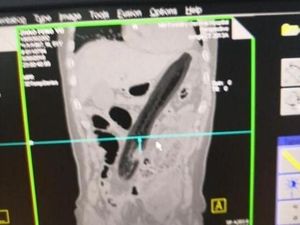

Seorang wanita mengalami amnesia sementara akibat mengejan terlalu kuat. Memori wanita yang sempat mengalami sembelit tersebut kembali normal setelah 8 jam.